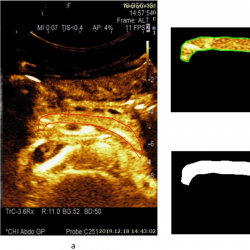

infor453_g003.jpg

Fig. 3

Example of a CEUS image (15 s after injection of contrast agent) of a healthy pancreas (healthy volunteer – female) and estimated area of a healthy parenchyma (according to the presence of perfusion): a – contrast harmonic image of the pancreas region and manually selected ROI according to the solid red line, b – extracted informative ROI for further automatic detection of healthy parenchyma areas being marked with a solid green line, c – automatically detected area of a healthy parenchyma is binary marked (white) and covers 100.0% of the overall pancreas ROI.

infor453_g004.jpg

Fig. 4

A CEUS image of a pancreas at 22 s after injection of contrast agent, and estimated area of a healthy parenchyma (according to the presence of perfusion) from a male patient with acute necrotizing pancreatitis: a – contrast harmonic image of the pancreas region and manually selected ROI marked with a solid red line, b – extracted informative ROI for further automatic detection of healthy parenchyma areas marked with a solid green line, c – automatically detected area of a healthy parenchyma (white colour) covering 55.6% of overall pancreas ROI.

An example of a CEUS image of a healthy pancreas (healthy female volunteer) acquired at 15 s after injection of contrast agent and an estimated area of healthy parenchyma (according to the presence of perfusion) is presented in Fig. 3. The automatically detected area of healthy parenchyma is marked in white, with the area covering 100.0% of the overall pancreas ROI. The CEUS B-mode image of pancreas affected by acute pancreatitis (male patient) acquired 22 s after injection of contrast agent, and an estimated area of healthy parenchyma (according to the presence of perfusion) is presented in Fig. 4. Here, the automatically detected area of healthy parenchyma (white) covers 55.6% of the overall ROI. The remaining part of the tissue is affected by necrosis and covers 44.4% of the overall ROI.